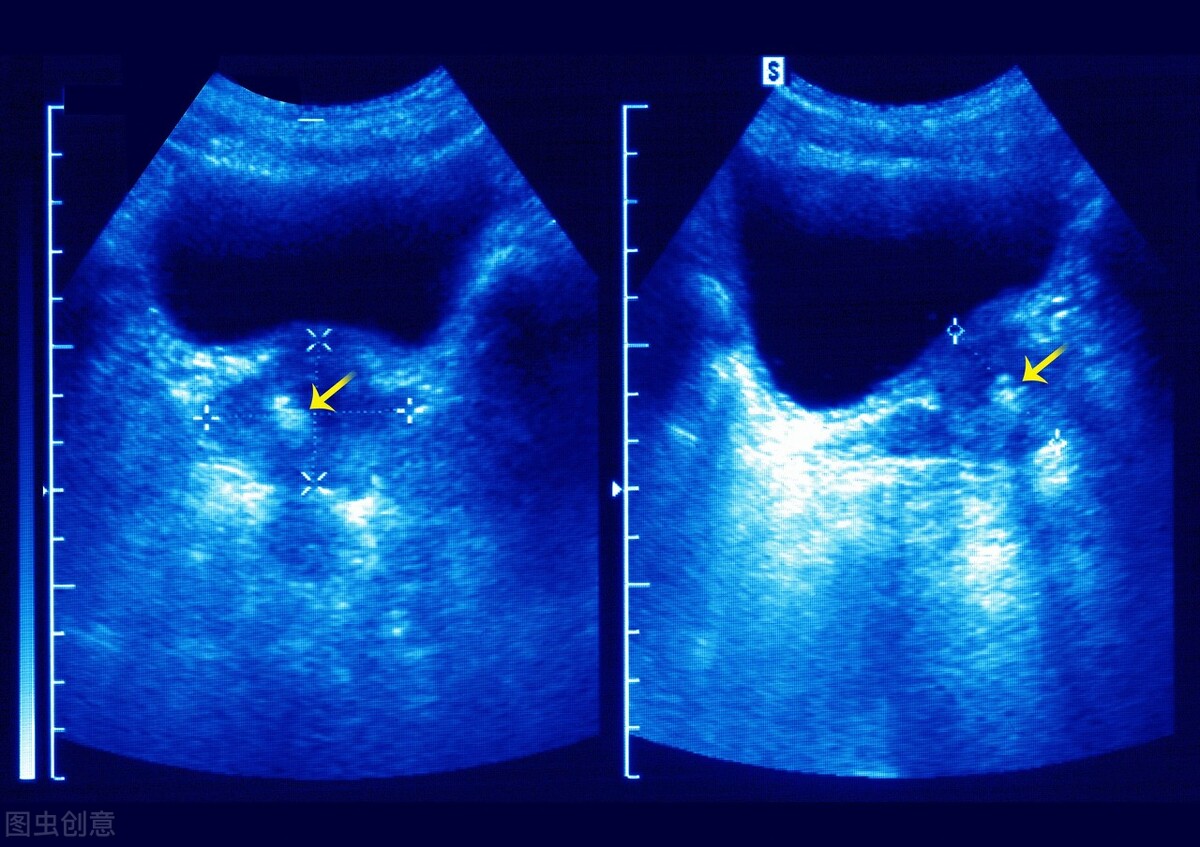

前列腺钙化,也叫前列腺钙化灶,其实并不是一个单独的疾病,而是在B超下看到的前列腺内钙质沉积现象。

前列腺钙化跟尿路结石的形成差不多,前列腺内有分泌物残留沉积,形成钙化的结晶体;或者是前列腺有过炎症,治好之后留下疤痕,也会发现前列腺钙化的情况。

前列腺钙化不会引起任何症状,对生育能力也没有影响。但是,前列腺钙化跟前列腺炎密切相关。前列腺炎患者,容易出现前列腺钙化;前列腺钙化也容易诱发前列腺炎。